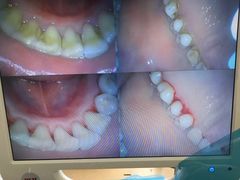

• 赫尔森口腔·牙齿种植修复

• -赫尔森口腔·牙齿种植修复